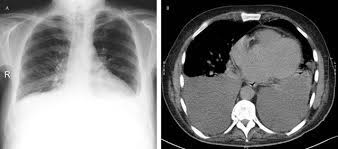

Figure 1 From Primary Pleural Synovial Sarcoma A Rare Cause Of Hemorrhagic Pleural Effusion In A Young Adult Semantic Scholar

Figure 1 From Primary Pleural Synovial Sarcoma A Rare Cause Of Hemorrhagic Pleural Effusion In A Young Adult Semantic Scholar from d3i71xaburhd42.cloudfront.net